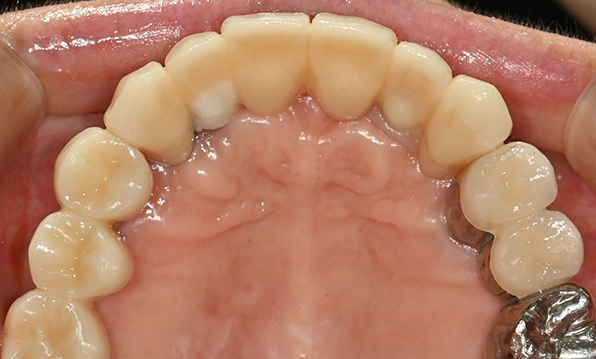

치아가 하나도 남아있지 않거나 전체적으로 상실된 경우 추천합니다.

전체 임플란트가 필요한 경우

치아가 얼마 남아있지 않은 경우

치주질환이 심해, 치아가 있더라도 제 기능을 하지 못하는 경우

틀니 사용이 불편한 경우

치료기간 : 2021.04.12~2021.09.15